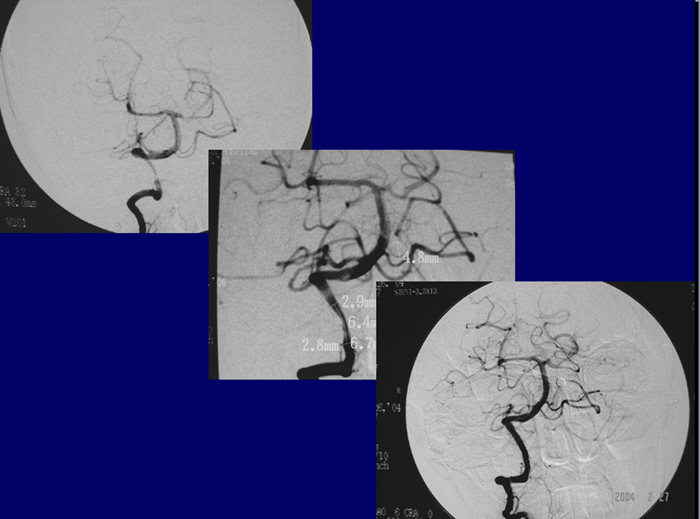

反复TIA或中风,经正规药物预防无效,无严重神经功能障碍。

无症状者,狭窄>70%;有症状者,狭窄> 50%;TCD显示远段低波动性(PI指数小于0.4); 由SPECT/PWMRI/PET其中之一证实局部相关脑组织缺血。